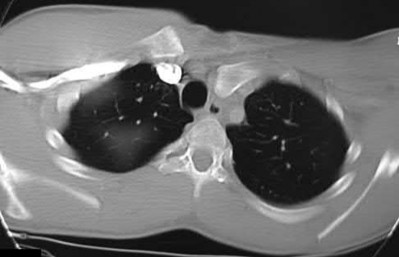

During head-on motor vehicle collisions occurring at highway speeds, airbag-protected individuals have a decreased rate (as compared to non-airbag protected individuals) of all of the following EXCEPT:

Corrent answer: 4

The referenced study by Loo et al. studied the interaction between airbags/seatbelts and mechanism of the crash (ie. front vs. side impact) and the injury patterns in these patients. They found that in frontal crashes, airbags reduced Glasgow Coma Scale severity in brain injury, facial fracture, shock, thoracoabdominal injuries and the need for extrication. Frontal airbags also had a protective effect on lower extremity fractures, but had no significant protective effect on pelvic fractures.